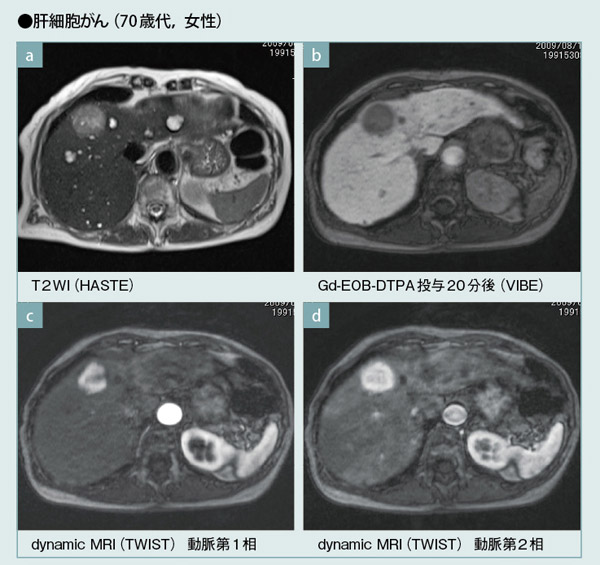

3T MRIにより,HASTE法でも肝細胞がん検出に必要なコントラストが得られ(a),20分後の肝細胞相の画質も向上している(b)。syngo TWISTを用いて,動脈相5相のdynamic MRIを行うことにより,腫瘍の血行動態の把握が可能である(c,d)。